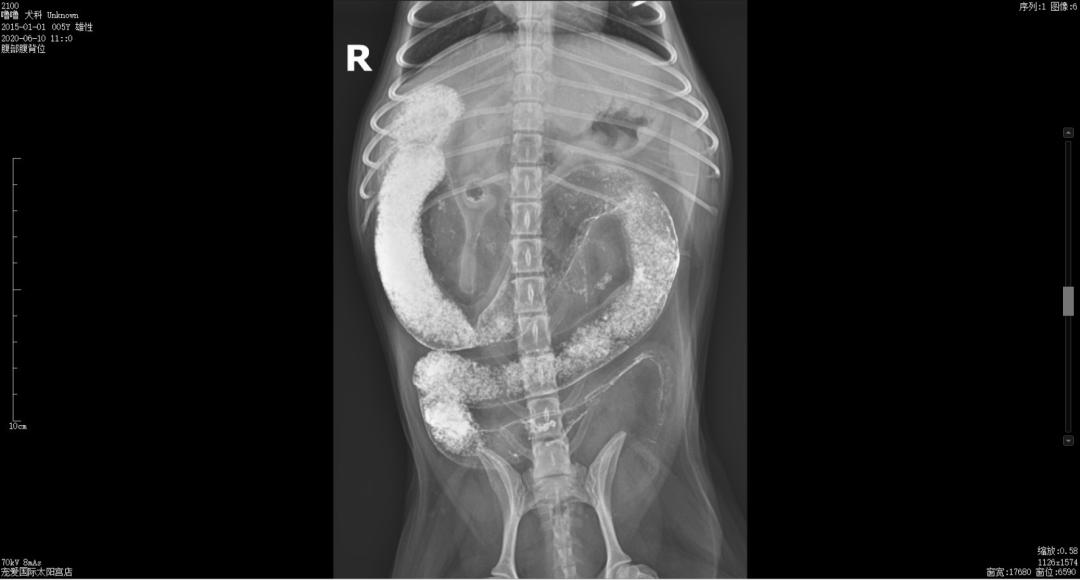

钡餐造影

常规打开腹腔,发现肠道因气体而扩张,找到异常肠道发现异物位于空肠内,在异物远端外健康肠组织处切口,用手术刀或者手术剪延肠管长轴打开切口,以便取出异物但不会撕裂肠道,取出异物后,修整外翻黏膜层边缘使其与浆膜层对齐,纵向或者横向对接切口,进行全层简单间断缝合,在距边缘2mm处全层缝合肠壁,进针时全层穿透轻轻上挑针尖并退针至黏膜层滑出,在从对侧黏膜-黏膜下层结合层进针,进针前针尖轻轻下压使黏膜层内翻,小心系紧每根缝线,不要切割肠壁层,轻轻对接不要压碎组织。缝线选择优选可吸收单丝线(多丝线阻力大,吸渗作用大,炎症反应大),如果动物ALB<2g/dL时,可以考虑使用不可吸收单丝线,再以大网膜覆盖于肠切口的周围,关闭腹腔,缝合皮肤。